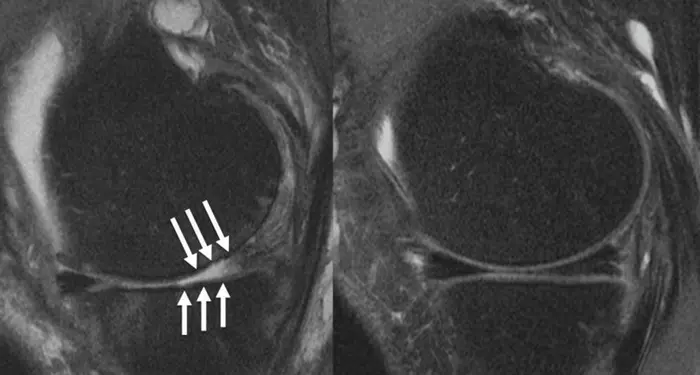

The researchers obtained 3T MRI of the thigh at the time of surgery. They also evaluated MRI findings from two years and four years before the surgery. They used a previously trained deep-learning model to segment and compute volumes of the muscles of the thigh—measures that are tedious to compute manually.

Comparing patients who had total knee replacement with the control group, a higher ratio of quadriceps to hamstring volume was significantly associated with lower odds of total knee replacement. Higher volumes of hamstrings and gracilis, a long, thin muscle on the inside of the thigh, were also linked with lower odds of total knee replacement.